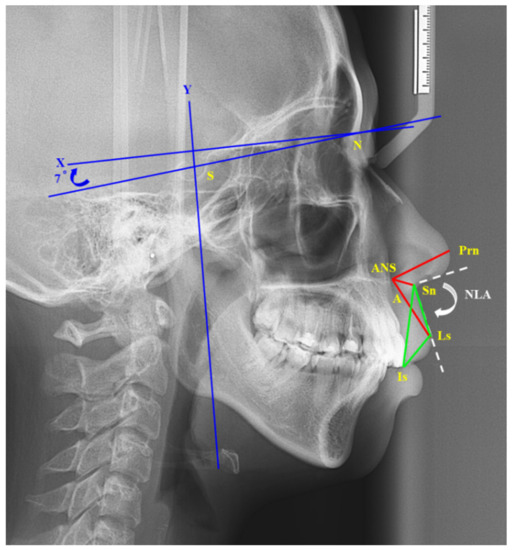

For quantifying volumetric changes in postoperative facial edema, van der Vlis et al. [17] used 3D stereophotogrammetry to measure the postoperative swelling after orthognathic surgery. They found that facial edema resolves approximately 80% during the first 2 months. Usually, the patient was referred to the orthodontist to begin orthodontic treatment at the postoperative 2 months. To reduce the effect on the surgical outcome by orthodontic treatment, the cephalograms were obtained before the operation and 2 months postoperatively. The following landmarks (Figure 4) were recorded: sella (S), nasion (N), point A, pronasale (tip of nose, Prn), subnasale (Sn), labrale superius (Ls), ANS, and incisor superius (Is). The x-axis (horizontal line) was constructed by drawing a line through N and 7° above the NS line, and the y-axis (vertical line) passed through S and was perpendicular to the x-axis. The following distances and angles were measured: ANS–Prn, ANS–Sn, ANS–Ls, Is–Sn, Is–Ls, and nasolabial (NLA) angle.

Figure 4.

Cephalometric landmarks: sella (S), nasion (N), point A, pronasale (tip of nose, Prn), subnasale (Sn), labrale superius (Ls), anterior nasal spine (ANS), and incisor superius (Is). The X-axis (horizontal line) was constructed by drawing a line through N and 7° above the NS line, and the Y-axis (vertical line) passed through S and was perpendicular to the X-axis. The following distances and angles were measured: red line: ANS–Prn, ANS–Sn, ANS–Ls; green line: Is–Sn, Is–Ls, Ls-Sn; white dotted line: nasolabial (NLA) angle.